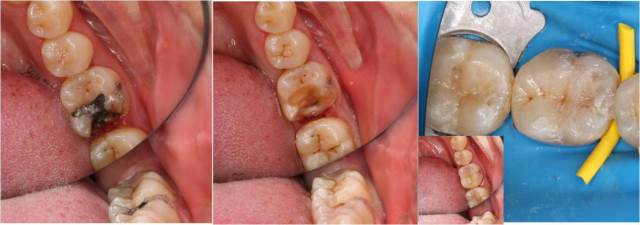

图:龋坏、继发龋坏、牙体缺损的直接美学修复

我科一直秉承细致严谨、微创舒适的原则。开展了龋病微创美学充填,其他各类复合树脂美学修复,渗透树脂治疗早期龋和牙釉质白垩斑,牙体冷光美白术,激光去龋,激光根管消毒,激光牙本质脱敏等一系列牙体保存、牙体缺损修复、和牙体美容项目。